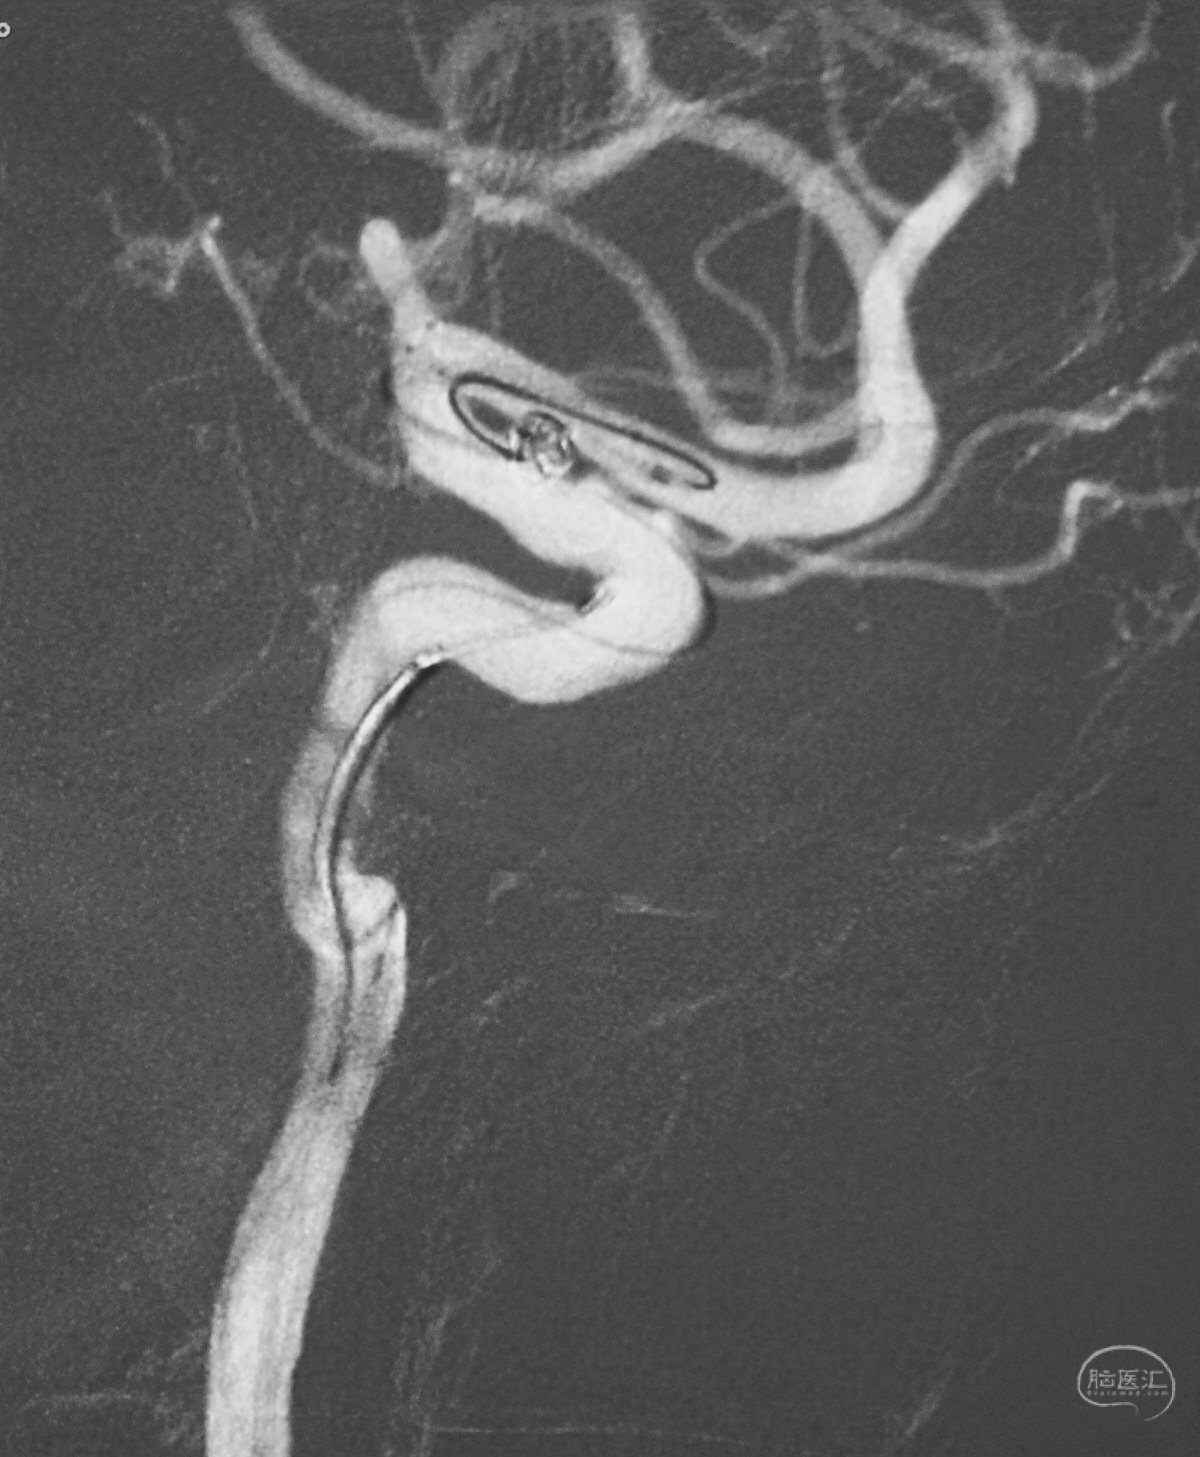

依次送入QC-2-4-3D,2-3-Helix,1.5-2-Helix,1.5-2-Helix四枚弹簧圈,最后一枚弹簧圈将管头(箭头)顶出瘤腔。

将Traxcess 14微导丝送入微导管,稍向远心端送微导管,使管头远离动脉瘤,再缓慢撤离。

解脱第一枚Solitaire 4×20支架后,套叠置入第二枚Solitaire 4×20支架,置入两枚支架的原因是考虑该瘤是夹层动脉瘤,多支架能够强化血流导向作用,有利于夹层愈合。